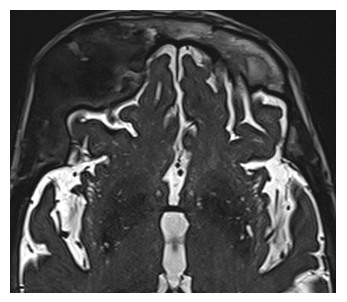

MRI imaging revealed an expanding abnormal growth impacting the upper part of the right eye socket and the right sphenoid bone, showing restricted diffusion. Altered signals were also detected in the sphenoid bone (Figure 5A). Furthermore, CT scans indicated an enlargement of the diploic space with a predominantly ground glass appearance, suggesting fibrous dysplasia changes (Figure 5B).